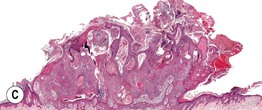

• Clinical term for marked hyperkeratosis arising from a papule or nodule (Fig. 89.10).

Fig. 89.10 Cutaneous horn. A This cutaneous horn arose from an actinic keratosis. B Striking column of hyperkeratosis with hyperplasia of the underlying epidermis. B, Courtesy, Luis Requena, MD.

• The base of the lesion most commonly represents an actinic keratosis, seborrheic keratosis, verruca, or squamous cell carcinoma.